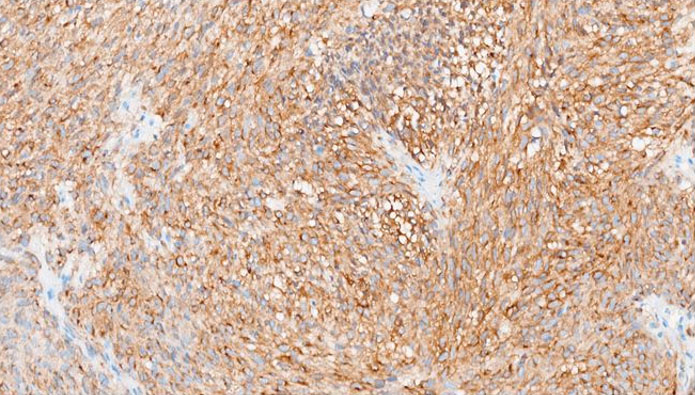

The formalin-fixed, paraffin-embedded (FFPE) tissue block from the previous biopsy was retrieved from the primary laboratory and then reviewed the histology at our facility, which revealed a tumor composed of spindle cells with fairly eosinophilic cytoplasm, inconspicuous nuclei, and rare abnormal mitoses (Figure 3). Immunohistochemically, the tumor cells were strongly positive for CD34 (Figure 4), CD117 (Figure 5), and DOG 1 (Figure 6).

Figure 4: Photomicrograph showing positive immunohistochemistry staining with CD 34 (× 200 magnification).

The tumor in our case report had a spindled morphology and was positive for CD34, CKIT, and DOG 1 immunostains.

CD34 is a transmembrane glycoprotein widely used as an immunohistochemical marker to identify hematopoietic stem cells, vascular endothelial cells, and stromal fibroblasts, as well as various neoplasms, spindle cell tumors (e.g., dermatofibrosarcoma protuberans, solitary fibrous tumors), and gastrointestinal stromal tumors (GISTs) [9],[13],[14]. Various studies emphasize its utility in diagnosing solitary fibrous tumors (SFTs) and its variable expression in GISTs, where it is positive in up to 83% of the cases [15]. CKIT is expressed in 80–95% of GISTs, showing cytoplasmic and membranous immunostaining with a characteristic perinuclear dot-like pattern [5]. CKIT IHC helps differentiate GISTs from other soft tissue neoplasms that may stain positive with cd34 on IHC [16]. Tyrosine kinase inhibitors (TKIs), such as Imatinib, Sunitib, Regorafenib, and Ripretinib, are first-line therapies for KIT-mutant GISTs. The commonly used drug has been Imatinib, demonstrating very excellent response rate in patients with KIT mutated GISTs [17]. Additional markers like DOG1 improve diagnostic accuracy, particularly in CKIT-negative GISTs [18]. DOG1 (Discovered On GIST 1), also known as ANO1, is a calcium-activated chloride channel protein that serves as a highly sensitive and specific immunohistochemical marker for gastrointestinal stromal tumors (GISTs). It is expressed in approximately 95% of GISTs, including those lacking KIT or PDGFRA mutations, making it particularly useful for diagnosing KIT-negative cases [18]. Beyond GISTs, DOG1 is also expressed in normal tissues such as interstitial cells of Cajal, salivary gland acini, prostate basal cells, and kidney distal tubules, as well as in tumors like esophageal squamous cell carcinoma, salivary gland tumors, chondroblastoma [19],[20],[21]. This therefore suggests that DOG1 is only linked to a diagnosis of GIST in spindle cell tumors, with numerous differential diagnoses in DOG1 positive epithelioid neoplasms.